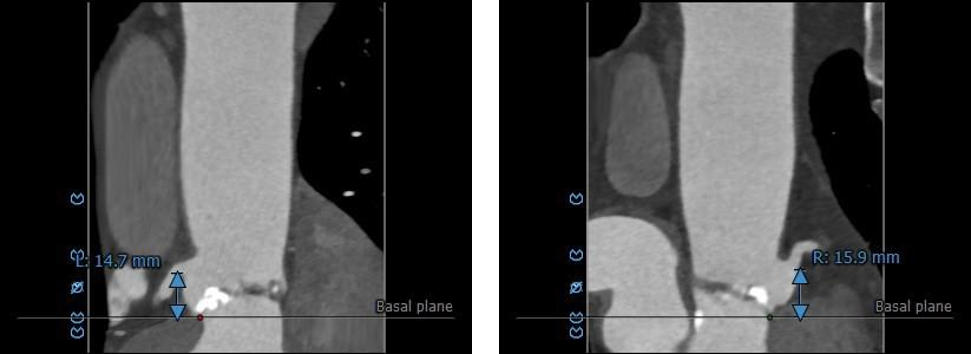

血管入路评估: